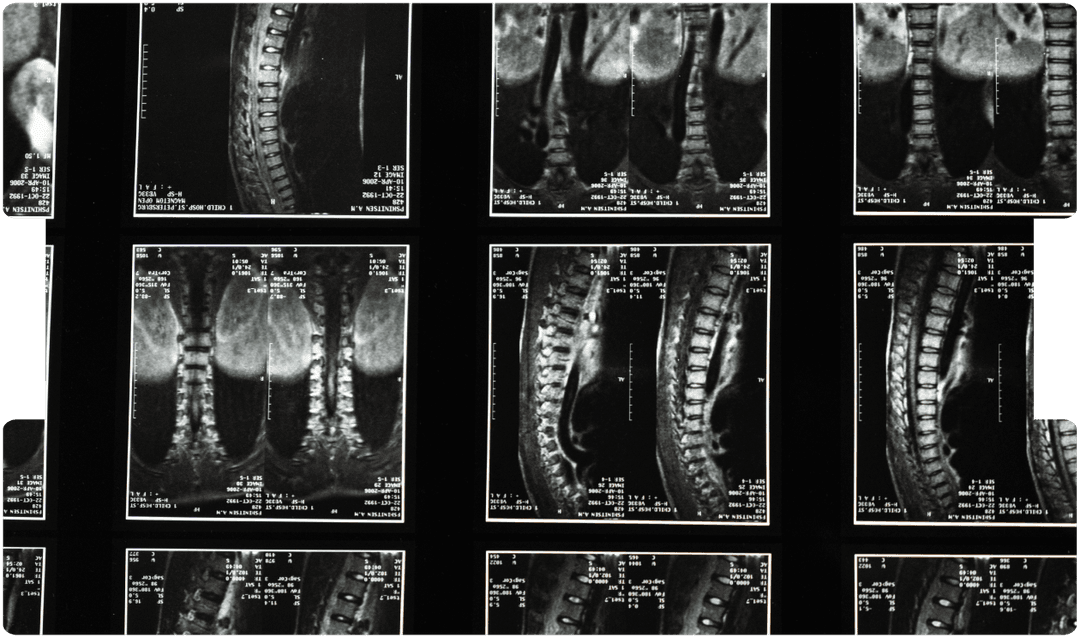

When MRI Doesn’t Match Symptoms: Chronic Pain & Legal Causation

By Dr Rajiv Malhotra, Consultant in Pain Medicine